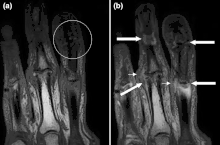

Magnetic resonance images of the fingers in psoriatic arthritis. Shown are T1-weighted (a) pre-contrast and (b) post-contrast coronal images. Enhancement of the synovial membrane at the third and fourth proximal interphalangeal (PIP) and distal interphalangeal (DIP) joints is seen, indicating active synovitis (inflammation of the synovial membrane; large arrows). There is joint space narrowing with bone proliferation at the third PIP joint and erosions are present at the fourth DIP joint (white circle). Extracapsular enhancement (small arrows) is seen medial to the third and fourth PIP joints, indicating probable enthesitis (inflammation of a tendon insertion). -